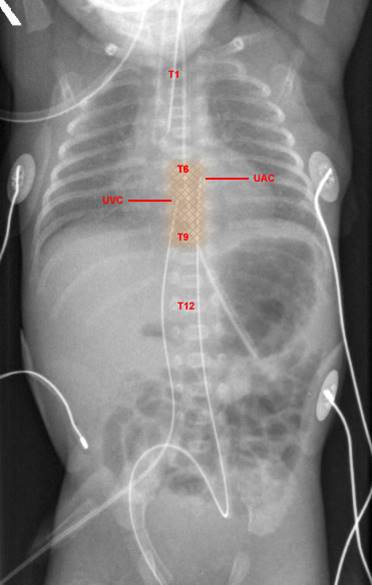

Bên cạnh đặt Catheter ở động mạch rốn để theo dõi huyết áp liên tục, tĩnh mạch rốn cũng cần đặt catheter để truyền thuốc cấp cứu suy tuần hoàn. Rốn là một trong những mạch trung tâm, việc truyền thuốc qua mạch trung tâm đỡ bị bít, tắc so với mạch ngoại vi. Một số loại thuốc, đặc biệt là thuốc dùng trong cấp cứu, chỉ truyền được qua mạch trung tâm, nếu truyền mạch ngoại vi sẽ dẫn đến co mạch, hỏng mạch. Do làm hai thủ thuật cùng một thời điểm, việc kết hợp đặt Catheter động mạch rốn và tĩnh mạch rốn giúp bé:

- Giảm số lần dùng an thần, giảm đau đớn và stress, giảm phơi nhiễm với nhiễm trùng

- Theo dõi được huyết áp động mạch liên tục, đo áp lực tĩnh mạch trung tâm giúp sử dụng thuốc cấp cứu chính xác, an toàn, hiệu quả

- Giúp lấy máu xét nghiệm qua động mạch rốn dễ dàng

Từ năm 2016 đến nay, khoa Sơ sinh Bệnh viện Phụ Sản Hà Nội đã đồng thời đặt Catheter động mạch rốn và tĩnh mạch rốn cứu nguy nhiều trường hợp suy tuần hoàn ở trẻ sơ sinh. Kỹ thuật này đã đạt giải Nhất trong “Hội thi kỹ thuật sáng tạo tuổi trẻ ngành y tế Hà Nội” năm 2017. Trong vòng một năm, khoa Sơ sinh của Bệnh viện Phụ Sản Hà Nội đã thực hiện 56 ca đặt Catheter tĩnh mạch rốn và động mạch rốn với tỷ lệ thành công chiếm 82,1%. Những trường hợp không đặt được nghi ngờ do động mạch bị xoắn, trong đó 1 trường hợp do trẻ sơ sinh 9 ngày tuổi, các mạch rốn đã đóng. Bệnh viện chưa ghi nhận trường hợp nào có biến chứng nhiễm trùng (nhiễm trùng Catheter, viêm ruột hoại tử), tim mạch (tắc mạch, loạn tim, huyết khối). Trường hợp viêm rốn, viêm phúc mạc, viêm ruột hoại tử, rối loạn đông máu nặng, thoát vị rốn, thoát vị qua khe hở thành bụng, có dấu hiệu tắc mạch chi dưới hoặc vùng mông được chống chỉ định với kỹ thuật này.